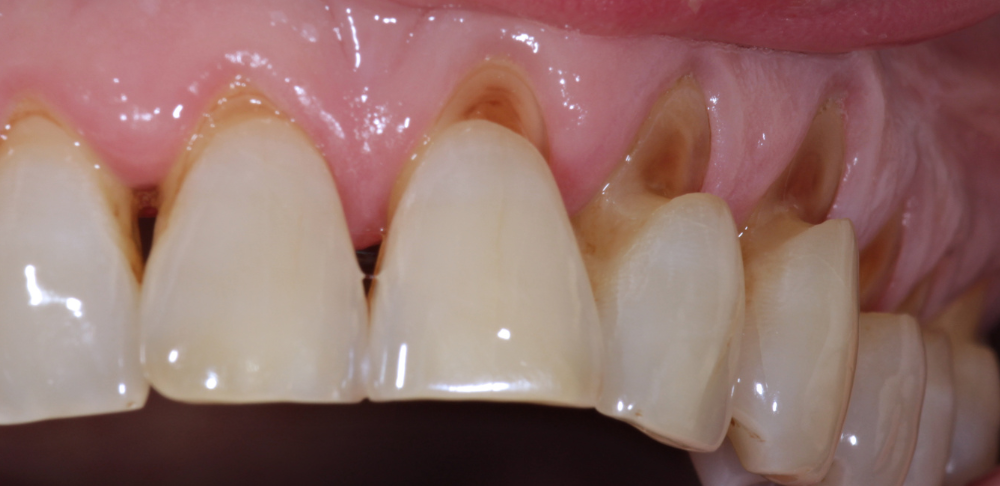

Pierwsze objawy ścierania zębów często można zauważyć samodzielnie. Jednym z nich jest widoczne spłaszczenie powierzchni zgryzowych, które tracą swoje naturalne wypukłości i zagłębienia. Zęby mogą wyglądać na „przycięte” lub krótsze niż wcześniej. Z czasem dochodzi także do zmiany koloru – ścierane szkliwo staje się cieńsze, a przez to bardziej przezroczyste. Odsłania się zębina, która ma żółtawy odcień i sprawia, że zęby wyglądają mniej estetycznie.

Innym symptomem może być pojawienie się nadwrażliwości na zimno, ciepło oraz na słodkie lub kwaśne pokarmy. Jeżeli podczas picia zimnej wody odczuwasz nieprzyjemne mrowienie lub ból, to może być znak, że szkliwo jest już uszkodzone. W lustrze można także dostrzec mikropęknięcia lub prześwity, szczególnie na krawędziach siekaczy.

Stomatolog podczas standardowego przeglądu potrafi rozpoznać ścieranie zębów na podstawie kilku charakterystycznych cech. Po pierwsze, analizuje kształt zębów i wysokość zwarcia. Jeśli zęby są zbyt niskie, a guzy zębowe starte – świadczy to o zaawansowanym ścieraniu. Lekarz może również zauważyć tzw. facety zwarciowe, czyli wypolerowane powierzchnie na zębach, które powstają na skutek ich intensywnego kontaktu.